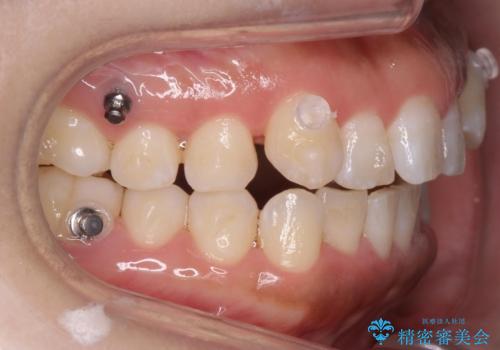

八重歯を非抜歯で マウスピースで治療 奥歯を後ろに下げてすき間を確保

- 八重歯を主訴に来院。

仕事柄ワイヤーが見えるよりはマウスピースで目立たなく歯並びを良くしていきたいとのことでした。

奥歯を後ろに下げてすき間を確保し、八重歯を引っ込めて並べる治療を行いました。

奥歯を後ろに下げるために、矯正用のミニスクリューを使用しています。